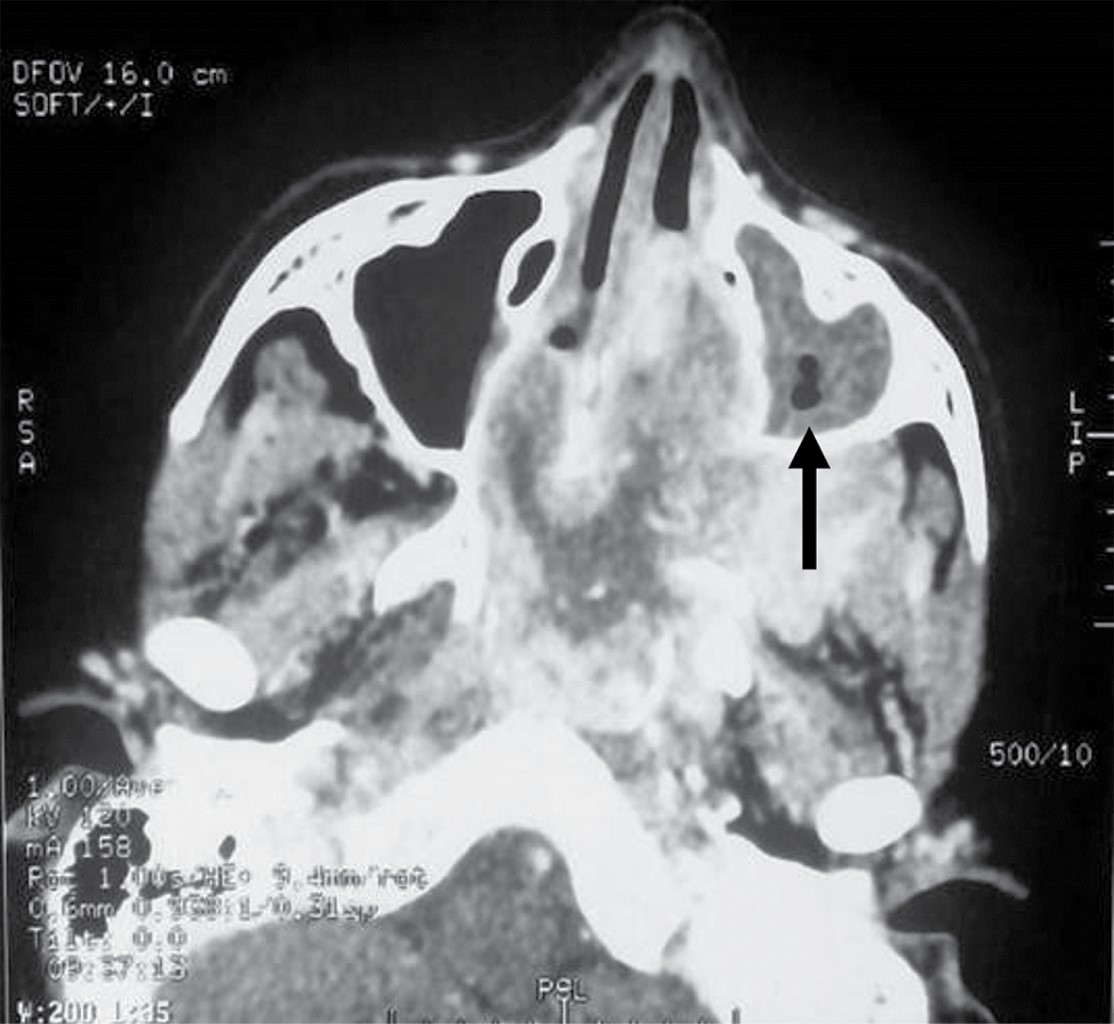

Introduction: juvenile nasopharyngeal angiofibroma is a benign tumor but can cause morbidity and mortality. We present a pediatric patient who had a successful resolution by surgical resection. Clinical case: ten-year-old male, with a history of nine months of unilateral nasal obstruction of approximately, associated with episodes of rhinorrhea, nocturnal hoarseness, mouth breathing, hyposmia and recurrent epistaxis. Imaging studies identified a tumor with irregular borders at the paranasal sinuses, concluding that it was a nasopharyngeal angiofibroma in stage IIb of the Radkowski classification. Tumor embolization is performed, and after 24 hours the tumor is removed by nasal endoscopic surgery. One year after resection, no tumor recurrence was documented. Conclusion: patients with juvenile nasopharyngeal angiofibroma are usually male, in the second decade of life, and with epistaxis as the main manifestation. Its treatment is surgical, with infrequent recurrences.

Figure 3